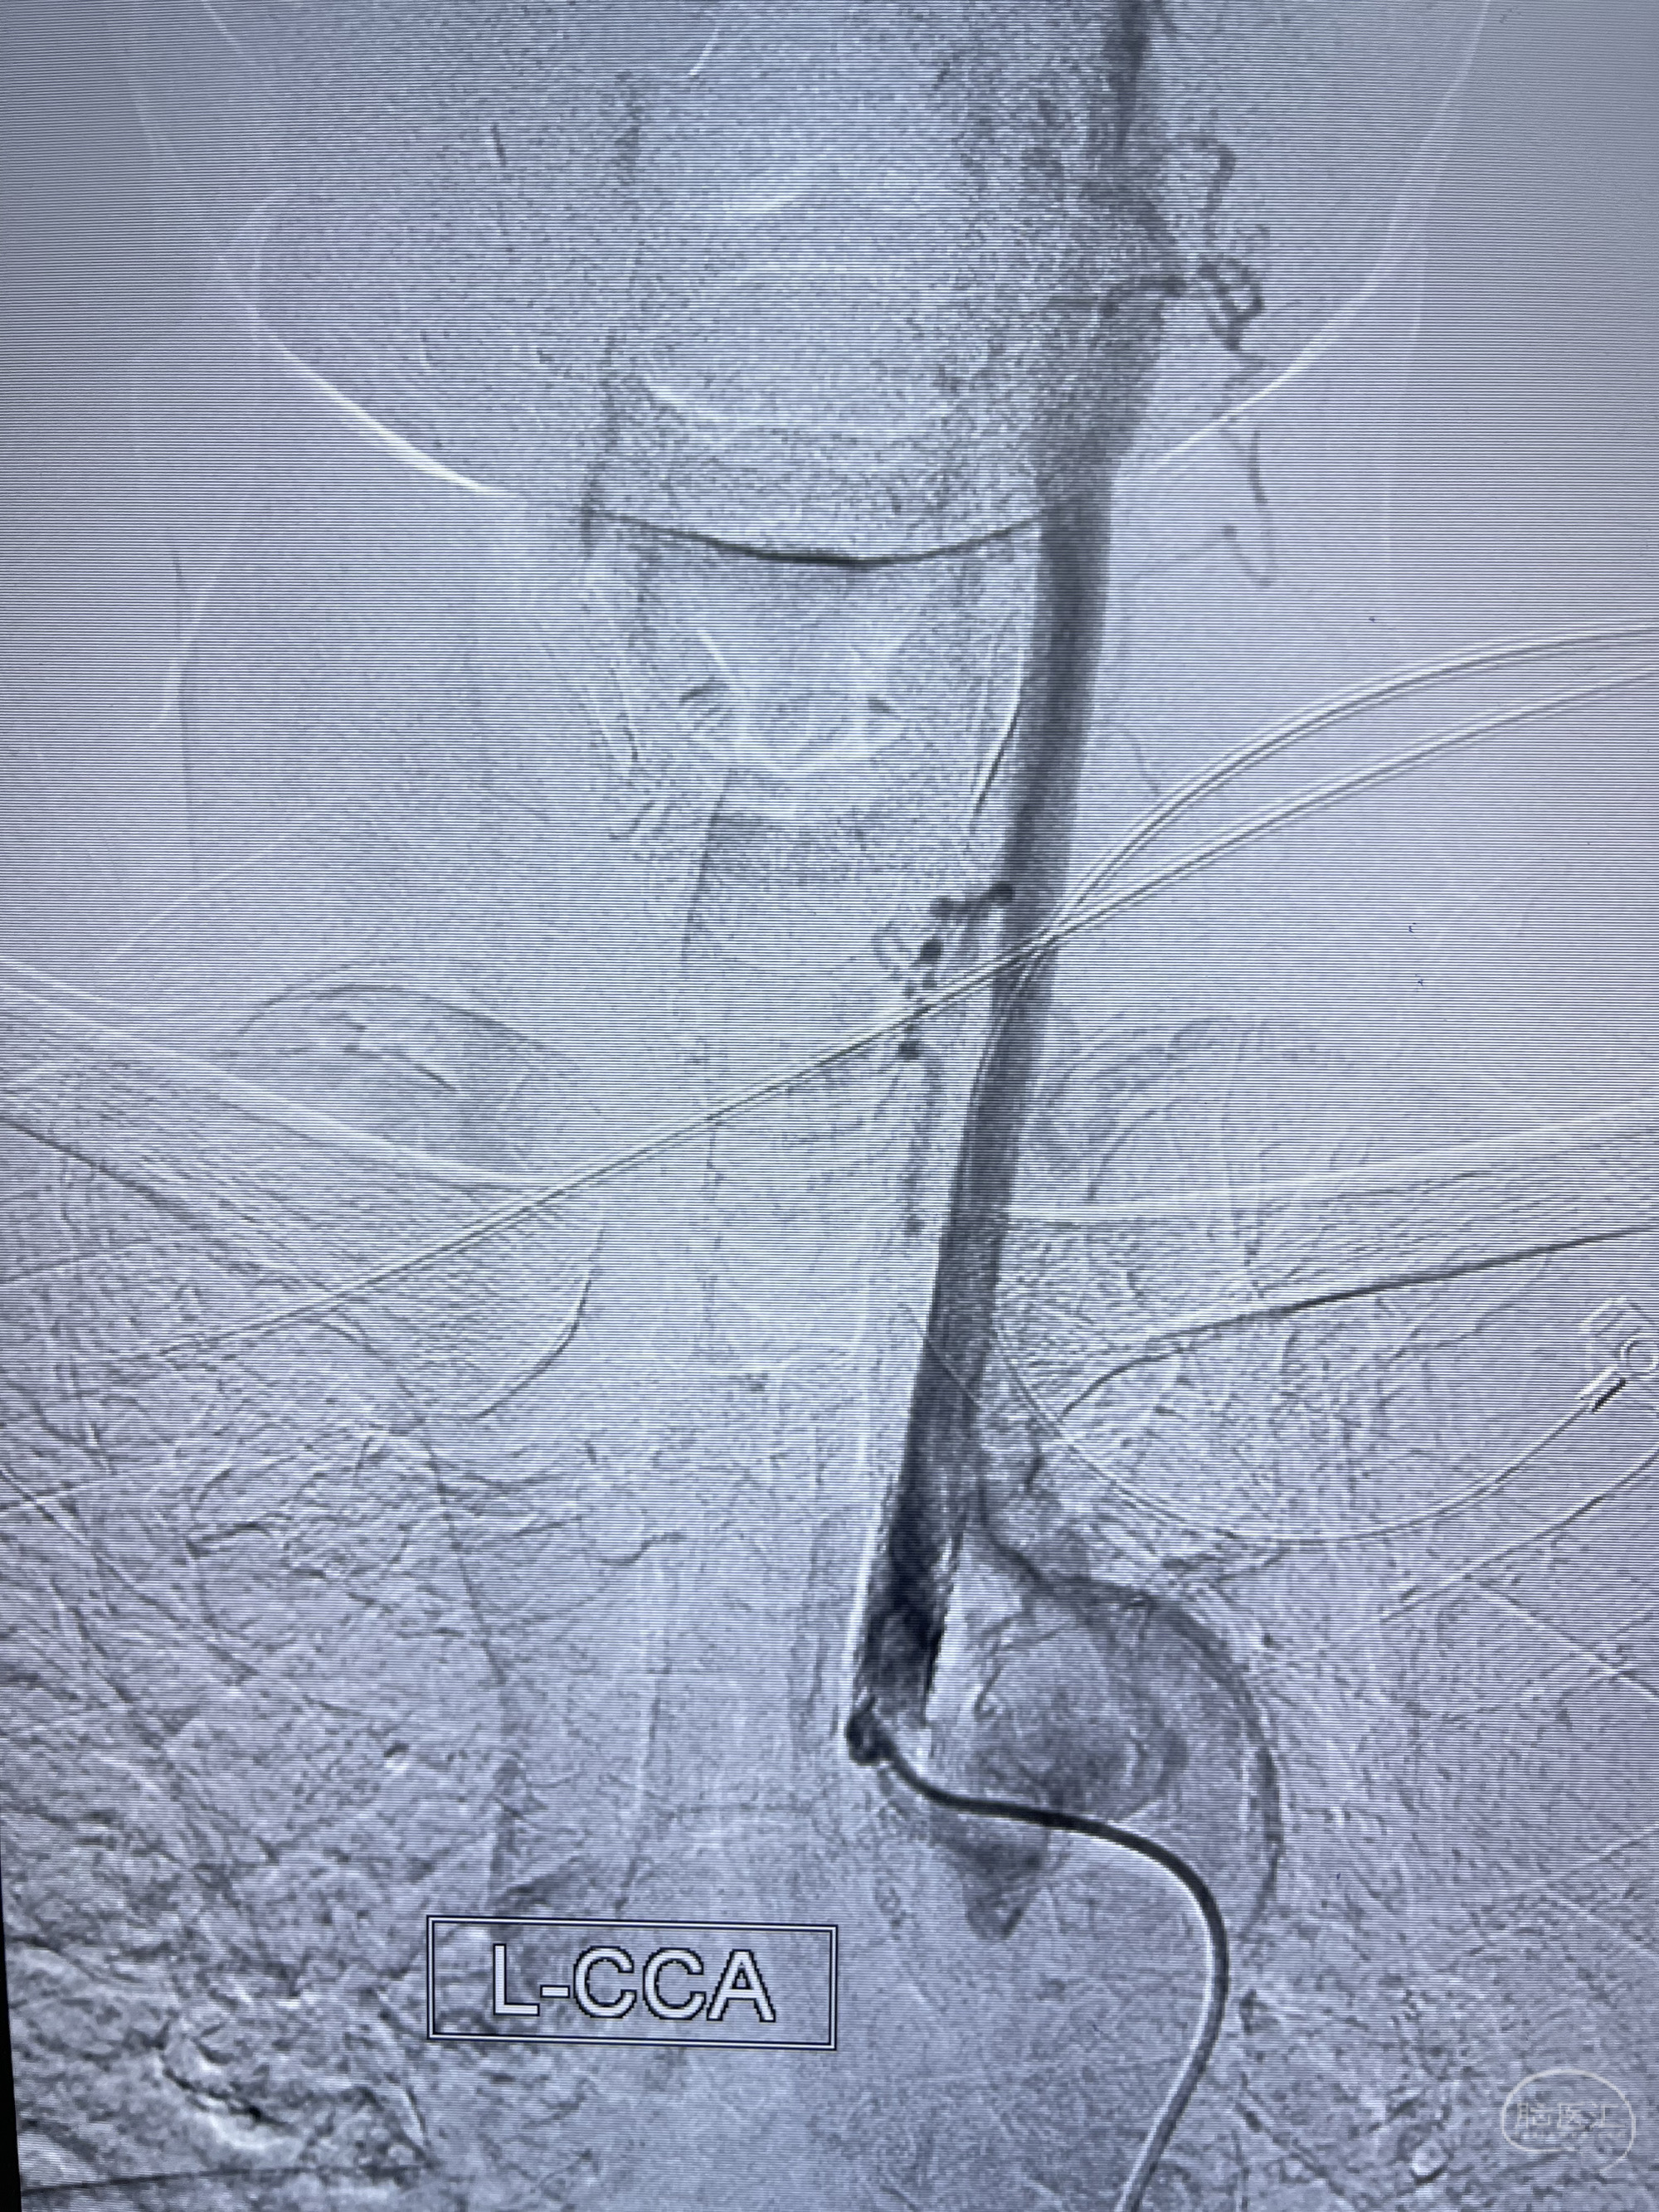

脑血管造影2023.03.06:右侧颈内动脉颈段至岩骨段闭塞,可见后后循环通过原始三叉动脉吻合代偿至海绵窦段,后交通区可见囊状造影剂填充影,左侧锁骨下动脉呈“残端”改变,呈“右侧颈总动脉支架成形术后改变”,支架内血流通畅,可见后交通吻合显影至左侧大脑后动脉,并可见左枕动脉吻合椎动脉至锁骨下动脉

2023-03-06DSA:

1.右侧颈内动脉及左侧锁骨下动脉闭塞

5.左侧颈总动脉起始部支架术后

6.左侧颈外动脉可见吻合显影至左侧椎动脉并逆行供血至左侧腋动脉

7.左侧锁骨下动脉闭塞

1.箭头处为右侧颈内动脉后交通动脉处重度狭窄,狭窄前壁为不规则动脉瘤;

2.狭窄远端颈内动脉由左侧颈内动脉经左侧后交通动脉—基底动脉顶—右侧后交通—右侧颈内动脉—右侧大脑中动脉途径代偿

左侧颈内动脉经左侧后交通动脉—基底动脉顶—右侧后交通—右侧颈内动脉—右侧大脑中动脉途径代偿

左侧颈外动脉经脑膜支吻合至左侧椎动脉—左侧锁骨下动脉—左侧上肢